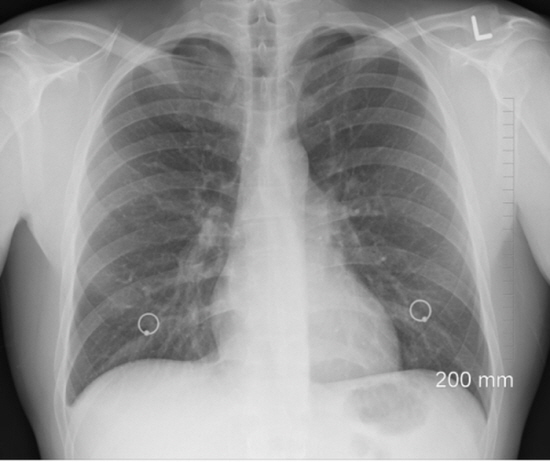

앗차! 싶었고 아무래도 갈비뼈 골절이 의심되어

정형외과에 가서 엑스레시 찰영결과

갈비뼈가 약간 금이 간게 발견이 되었습니다